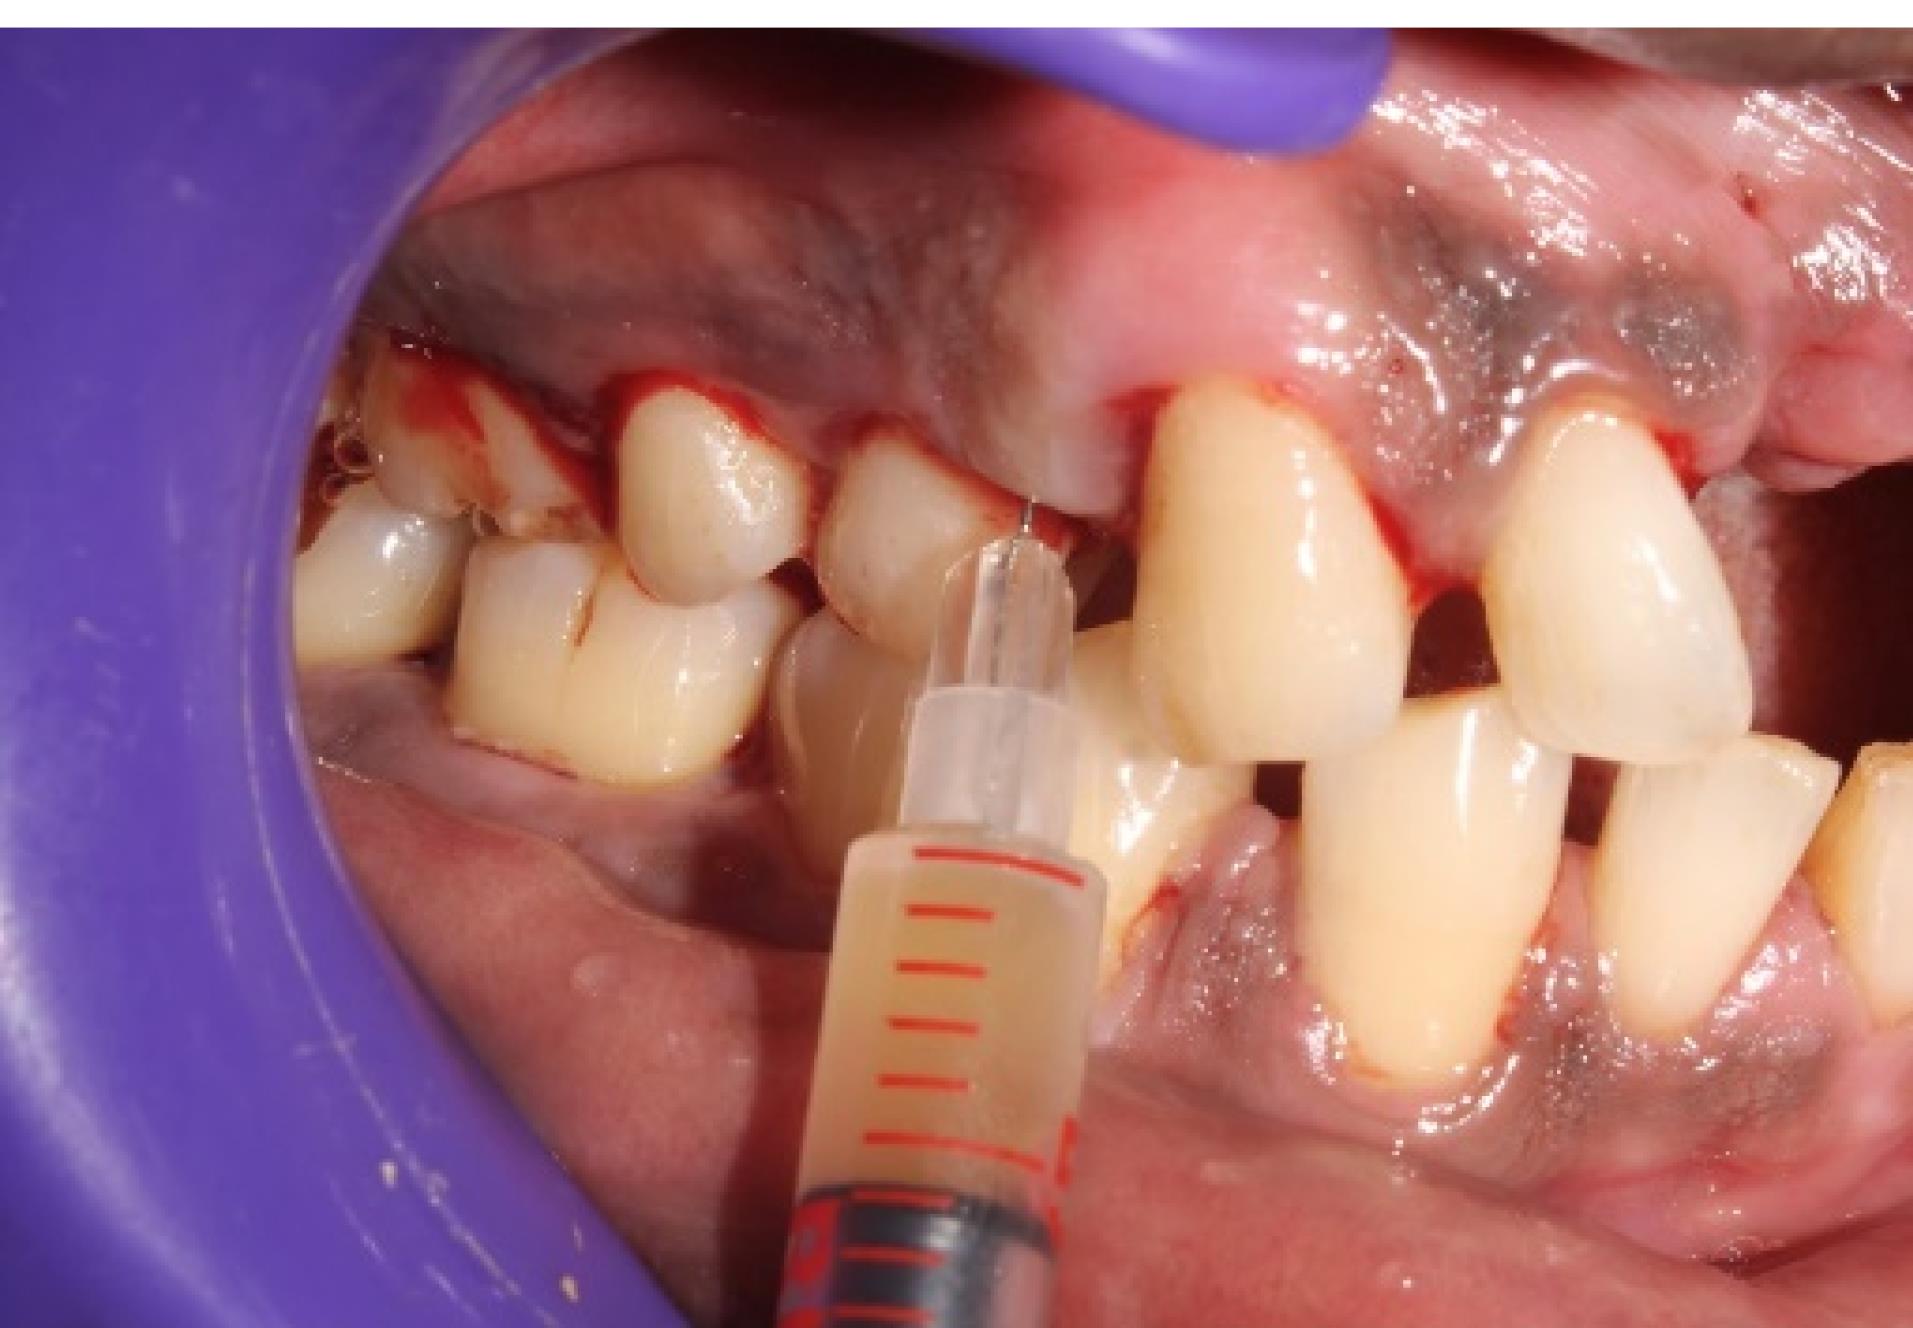

Local delivery of ciprofloxacin-loaded i-PRF

This mixture was further immediately loaded in a 1-mL insulin syringe (Figure 3) and injected into the periodontal pocket until it filled and overflowed followed by injecting into the tissues adjacent to the periodontal pocket before it became a gel in the participants of group 1 (Figure 4). In group 2 participants, plain iPRF was delivered at the experimental sites as explained above and allowed to gel. Postoperative instructions were given to all the study participants. There was no prescription for mouthwash or medications for any of the subjects, and they were asked to report after 6 and 12 weeks for follow-up.

Figure 4.

i-PRF mixed with ciprofloxacin injected into the periodontal pocket (group 1)